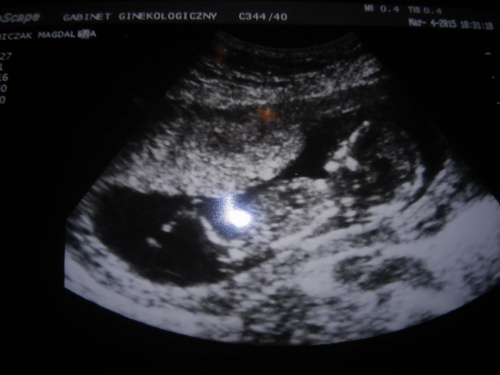

nick nieaktualnyHej jestem po badaniu prenatalnym. W zasadzie chyba wszystko dobrze, ale lekarz prosil mnie bym przyszla jeszcze raz za 3 tyg. Juz bez dodatkowych kosztow??? Nie wiem dlaczego??? Kurcze nie mogl znalezc przeplywow moich i dziecka, ale w koncu sie udalo,a widzialam ruszajace sie serduszko bylo piekne

nick nieaktualnyJa jeszcze jestem w szoku , ale mowil, ze nosek jest, ze przeziernosc karkowa ok, ma mozg, nerki i inne nazady, nozki, raczki??? Nie mam pojecia, moze sie nie ruszal i to go zaniepokoilo? Dal mi swoja wizytowke i zaprosil za 3 tyg.

Teraz sprawdzam NT 2,3 to chyba nie najlepiej prawda?

Misia NT 2,3 to dobrze od 2,5 wzrasta ryzyko, zresztą mój lekarz stwierdził, że samo Nt nie określa nic, dopiero razem z kością nosową i innymi pomiarami daje obraz sytuacji. Mój misiek też się zbytnio ruszać nie chciał na badaniach, kilka dni wcześniej jak byłam na wizycie to fikał koziołki a na badaniach leżał i spał i nawet energiczne potrząsanie brzuchem głowicą nic kompletnie nie dało. Tak więc nie martw się niepotrzebnie, na pewno jest wszystko w porządku